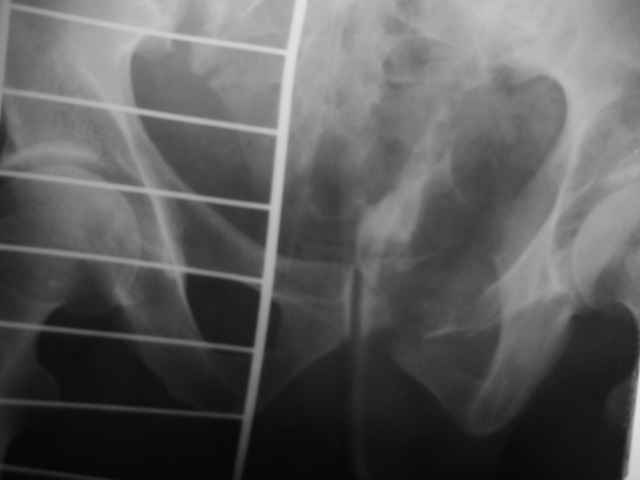

Можно посмотреть на нынешние снимки таза в аппарате, фас и inlet?

Отправитель: Владимир Бахарев 16 Ноябрь 2006, 12:13

Александр Николаевич! Походу самим не справиться (может к себе возмете, а?) Мы бы съездили к вам посмотрели как это делается!

Снимки вот

> (перелом лонной, седалищной костей справа . Разрыв КПС слева)

может быть и двустороннее повреждение задних отделов

по представленным рентгенограммам понять почти ничего невозможно из-за низкого качества, снимки идут в динамике? Для уточнения характера повреждения таза необходимо сделать хотя бы "inlet". повреждение представляется вертикально-нестабильным, в этом случае устранить краниальное и, возможно, передне-заднее смещение "передней рамой" невозможно и дело тут не в жесткости АВФ. Кольцевой опорой можно сделать все что угодно.